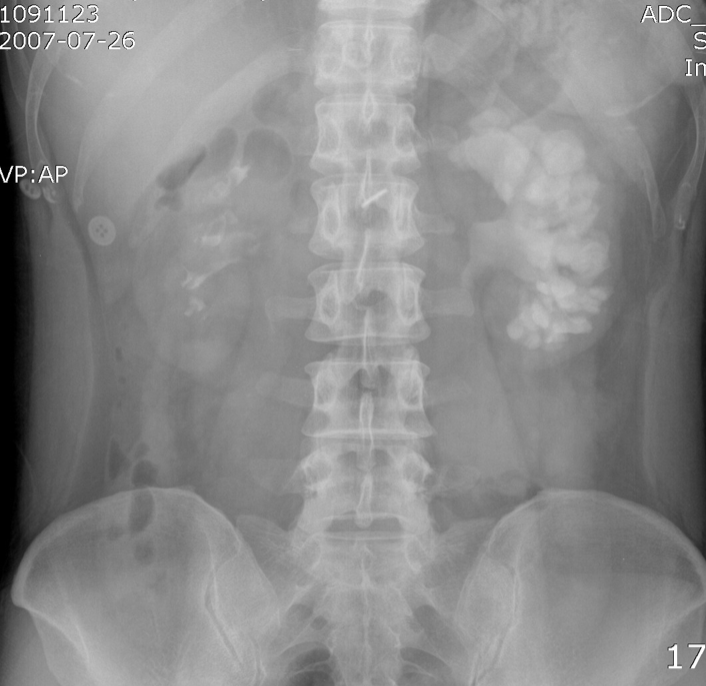

별로 멋지지 않은 제 사진을 공개합니다. 제 신장 사진이예요. 저는 한쪽 신장이 매우 큽니다. 신장이 크면 좋을 줄 알았는데, 나쁜 병이라고 합니다. 수신증이라고 하는데, 물 수(水)에 콩팥 신(腎), 즉 물 찬 신장, water kidney라는 뜻입니다. 소변의 통로가 막혀서 한쪽 신장에서 머물게 되어 고무풍선 마냥 부풀어 커집니다. 의학용어로는 hydro· nephrosis라고 합니다. 물을 뜻하는 hydro에 신장을 뜻하는 nephro와 상태를 뜻하는 ~sis를 붙여서 hydronephrosis라는 단어가 되었습니다.

저는 이 물 찬 콩팥 hydro·nephro·sis 때문에, 자꾸 돌찬 콩팥 Nephro·lithia·sis이 돼서 늘 걱정입니다. litho는 돌을 뜻하는 그리스어고, ~sis는 상태를 뜻하는 말입니다. 신장(nephro)과 돌(lithia), 그리고 증(~sis)로 구성된 단어입니다. 일반적으로는 신장 결석, kidny stone 혹은 renal stone이라고 하고, Nephrolithiasis는 점차 덜 사용되는 추세입니다. 좀 더 어렵고 옛스런 느낌의 단어죠. 한자용어 같은 느낌입니다. 돌을 뜻하는 다른 말로 Calculi를 쓰기도 합니다. 예, 칼슝의 그 calc~ 입니다. Kidney calculi, 역시 신장결석을 의미합니다.